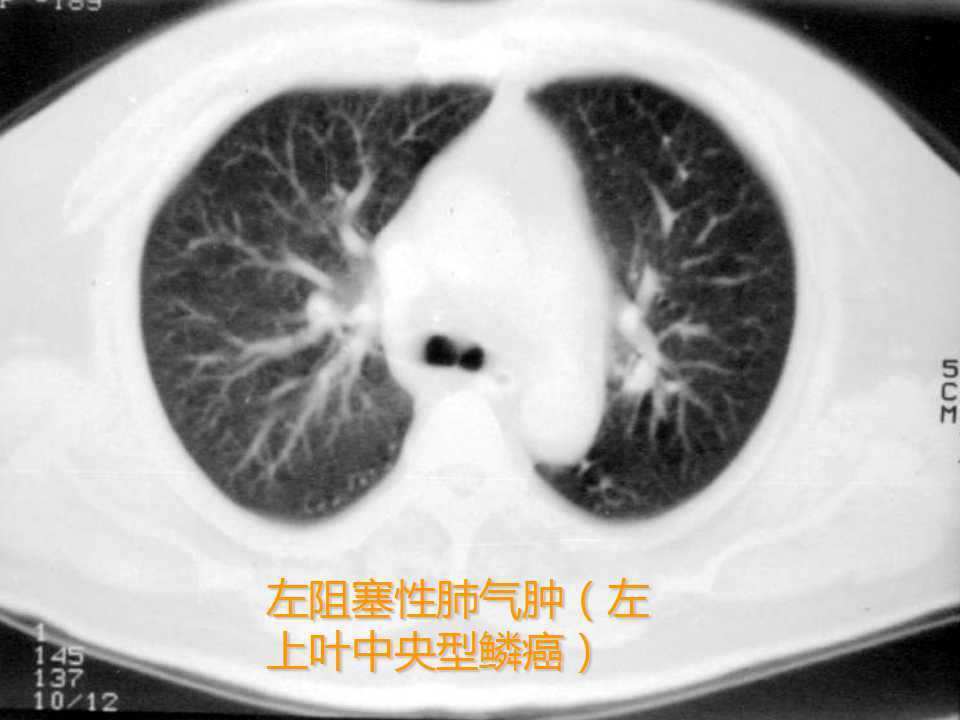

肺癌影像学表现